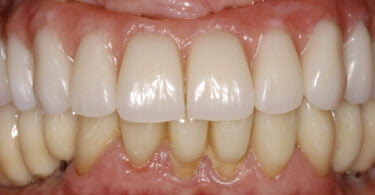

As seguintes imagens apresentam um dos casos incluídos no estudo (figura 03 – 15).